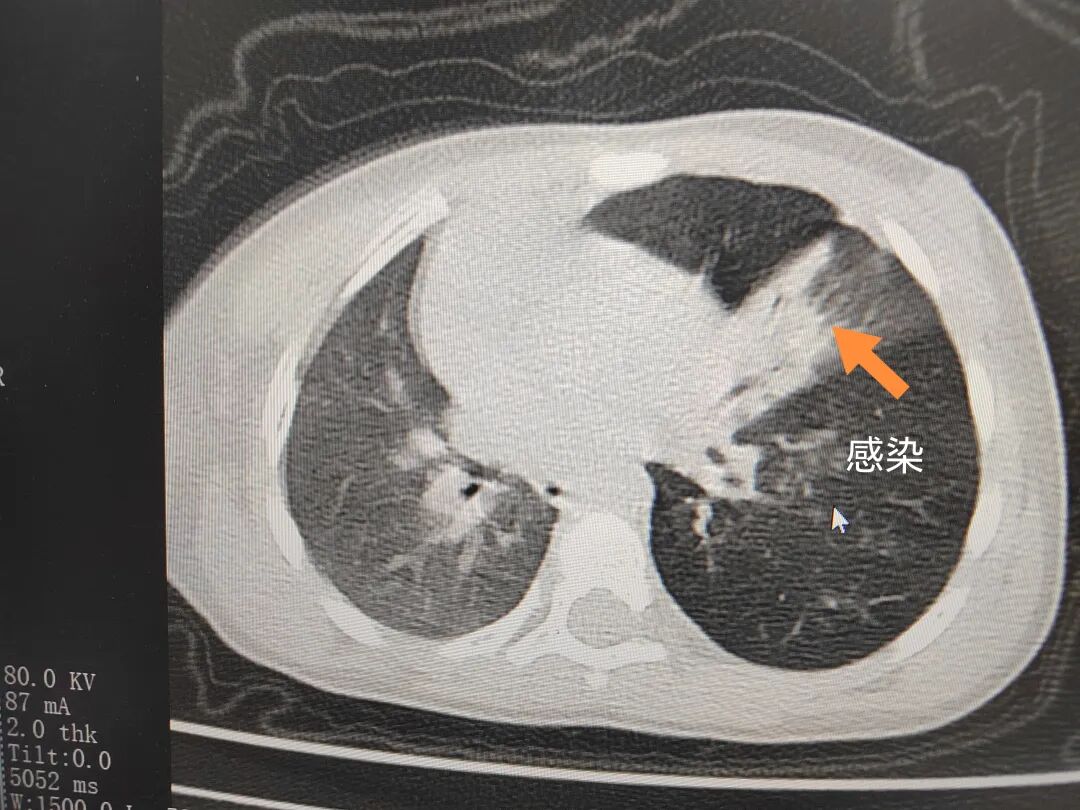

三天后(11月13日),趙寶出現(xiàn)高熱、咳喘加重,家長(zhǎng)著急了,再次帶他來(lái)到醫(yī)院。CT檢查顯示左肺過(guò)度充氣,左肺上下葉支氣管主干見不規(guī)則高密度影,左肺上葉可見大片狀密度增高影,縱隔窗實(shí)變,提示為“左側(cè)支氣管內(nèi)異物并繼發(fā)性改變,左肺上葉舌段肺膨脹不全”。

市二院小兒呼吸內(nèi)科副主任楊亞娟介紹,異物誤入氣道可能導(dǎo)致氣道阻塞,嚴(yán)重時(shí)可引發(fā)窒息,甚至危及生命。若異物進(jìn)入支氣管,造成不完全堵塞,可引起阻塞性肺氣腫;如完全堵塞支氣管,則可能導(dǎo)致肺組織萎縮,形成肺不張。此外,若異物存留時(shí)間較長(zhǎng),或?yàn)橹参镄援愇?,容易合并?xì)菌感染,產(chǎn)生膿性分泌物,進(jìn)而發(fā)展為肺炎。她強(qiáng)調(diào),盡早診斷并取出異物,是減少并發(fā)癥、降低病死率的關(guān)鍵。